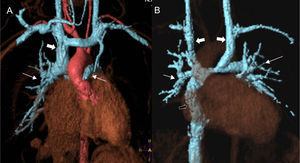

Processing images of angiography volumes through MRI in patients with systemic–pulmonary connection. In the patient with partial cavopulmonary connection or Glenn surgery (A) the superior cava vein (thick arrow) anastomoses with the right pulmonary artery (pulmonary arteries highlighted with thin arrows). The heart receives blood from the pulmonary veins and the inferior cava vein while working as a systemic pump only. After the total pulmonary connection or Fontan proceeding (B) the whole systemic venous circulation (except for the coronary sinus) directly irrigates the lungs through the cava veins. The patient has a double superior cava vein (thick white arrows) thus showing bidirectional Glenn anastomosis. The inferior cava vein connects to the right pulmonary artery through one duct (black arrow). The pulmonary artery (thin arrows) receives all its blood support from the systemic venous territory. The heart is still one systemic pump only but now getting the blood from the pulmonary veins.

Aorticopulmonary collaterals in univentricular correction (Glenn and Fontan procedures). Univentricular correction is a surgical procedure common to several heart conditions in which the functioning of the heart as a systemic and pulmonary pump is not possible. Depending on this or that heart condition there are different variants (Norwood, Damus-Stansel, Glenn, Fontan) but the common end to them all is total cavopulmonary connection (Fontan) in which the heart becomes a single systemic ventricle and the pulmonary arterial tree is directly irrigated by the cava veins. Usually in a first stage (at age 3 or 4 months) the superior cava vein is termino-laterally connected to the right pulmonary artery (Glenn procedure or partial cavopulmonary connection) (Fig. 6A). In a 2nd step approximately at the ages of 3–5 the inferior circulation is connected through one duct to the pulmonary artery (Fontan procedure or total cavopulmonary connection) (Fig. 6B). One of the complications of this procedure is the formation of aorto-pulmonary collaterals prior to the completion of the total correction during the years in which only partial cavopulmonary connection is in place (Glenn procedure). The physiopathology of this complication though not fully understood is attributed to the existence of a humoral factor (hepatic putative factor) that in these patients does not circulate across pulmonary vascularization when the inferior cava vein and the suprahepatic veins flow returns directly to the systemic arterial circulation without passing through the pulmonary blood vessels.